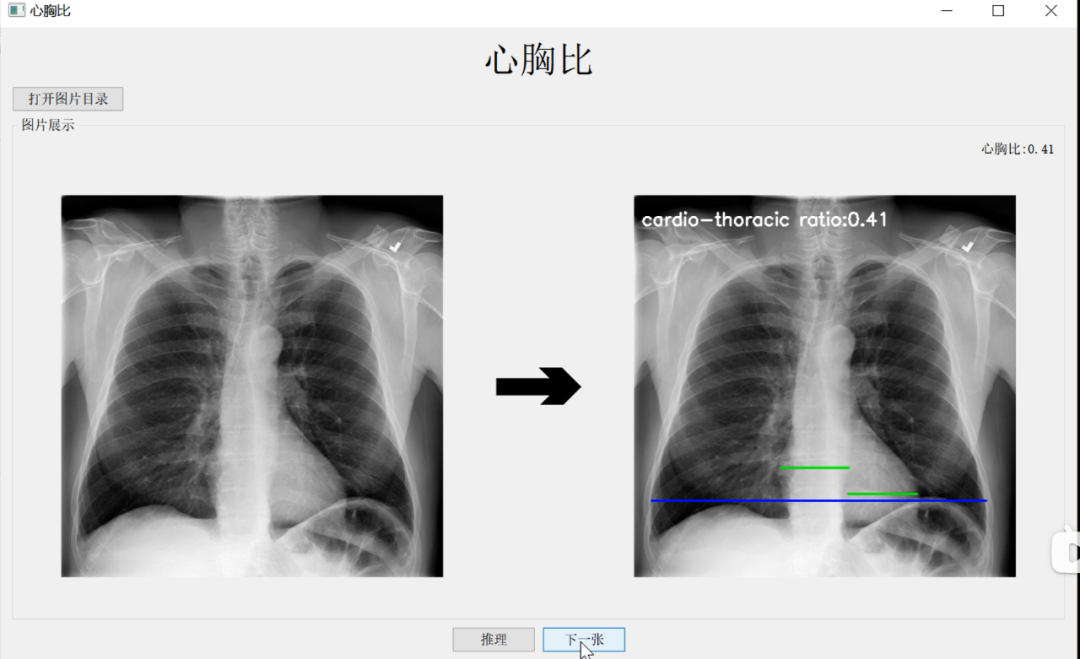

测心胸比从人工测量转向计算机视觉

他重点介绍了“快速测心胸比”项目。放射科医生在下诊断之前,会花费不少时间看医学影像图像,测量各种数据指标,从而更好地判断患者的病情。测心胸比是影像诊断中判断心脏是否增大的常用手段,心胸比是指在X线片上心脏横径与胸廓横径之比,一般成年人正常心胸比不大于0.5,如果心胸比大于0.5,说明心脏有增大的倾向,患者需要去做进一步的CT检查,确定导致心脏增大的原因。

医师手动计算心胸比需要先测量心脏最大横径

与肺部最大横径,再计算两者比率

通常,医院的放射医师手动测心胸比,一天可能要测四五百张,非常耗费时间。此外,由于人的肺部是一个不规则的生理结构,不是简单找到点到点的直径距离就能测出来。因而,人工测心胸比主观性强,容易有误差,可能不同的医生检测出来的结果也并不一样。

冯嘉骏选择使用PaddleSeg 2.0开发工具,实现自动准确测量心胸比,最终使得肺部和心脏的医疗图像分割精度结果分别达到了0.978和0.955的准确率。

作为计算机视觉领域重要的技术之一,图像分割将图像分成若干具有相似性质的区域,是图像语义理解的关键环节。冯嘉骏采取区域分割方法,基于飞桨图像分割套件PaddleSeg,借助其高精度和轻量级优势,将心脏和肺部两个器官的横径准确测量出来,目前该技术已经应用到农田分割、工业机器目标检测、医疗影像分割等领域。